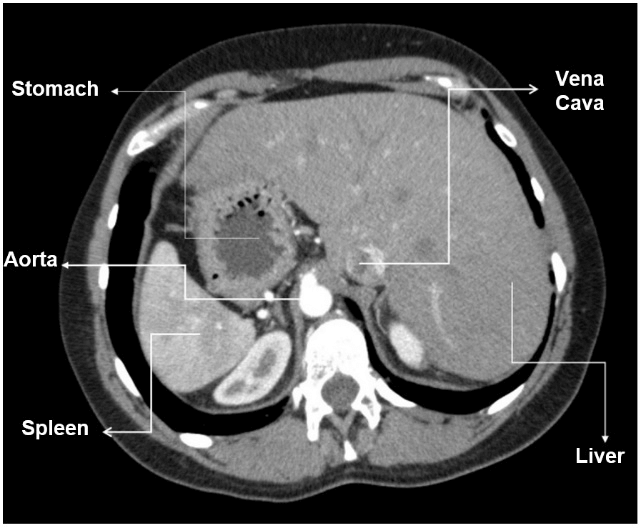

A chest X-ray revealed heart and stomach gas on the right side (Figure 1). A conventional transthoracic echocardiogram revealed dextrocardia without another abnormalities (Figure 2). A computerized tomography of the abdomen was performed and showed the liver on the left side, spleen and stomach on the right side. No other congenital malformations were found (Figure 3). Currently, the patient is 16 years old and under periodic systematic control at the Hematology and Cardiology services.

Figure 3: Computed tomography revealing stomach, aorta and spleen on the right side, vena cava and liver on the left side.